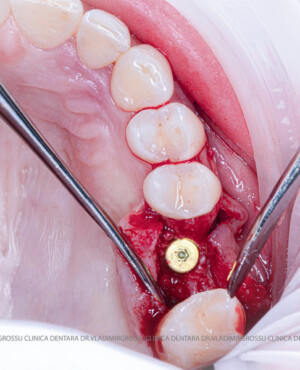

După extracția dentară, în intervalul de 6-12 luni, osul alveolar suferă un proces natural de remodelare, ceea ce conduce la scăderea volumului osos prin rezorbție. De aceea, inserția implantului dentar este ideală imediat după extracție sau, cel târziu, în primele 3-4 luni după aceasta.Scopul procedurilor de adiție osoasă este refacerea fundației osoase necesare pentru stabilizarea corectă a implantului dentar. Pentru ca un implant să reziste în timp la forțele masticatorii, este nevoie de o bază osoasă solidă și sănătoasă.

Un element esențial în procedura de aditie osoasă este utilizarea membranelor biologice, care izolează materialul osos de țesuturile moi (gingie) pe durata procesului de vindecare. Cele mai recomandate sunt membranele resorbabile din colagen sau pericard.

Aditia gingivală este o procedură chirurgicală ce corectează diverse probleme estetice și funcționale, cum ar fi recesiunea gingivală. În implantologia modernă, aditia de țesut moale este utilizată aproape în fiecare intervenție de inserție a implantului dentar pentru a asigura un aspect estetic natural și o bună integrare a implantului în cavitatea bucală.

Adiția osoasă are un rol crucial pentru poziționarea corectă și stabilă a implanturilor dentare. Clinica stomatologică Dr. Grossu din Chișinău promovează o abordare chirurgicală estetică și predictibilă, adaptată fiecărui caz în parte.

Medicii noștri au o vastă experiență atât în chirurgia estetică, cât și în protezarea cu un grad înalt de naturalitate, ceea ce ne permite să gestionăm cu succes și cele mai complexe cazuri.